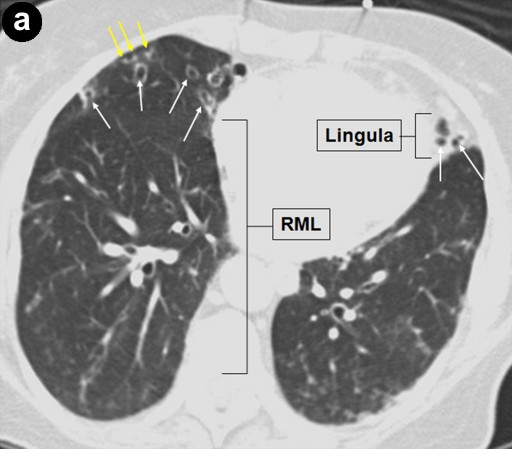

A 79-year-old asymptomatic women was found to have a serum CA 19-9 of 210 U/mL (reference range: 0-37 U/mL) during a general medical examination in 2000; the CEA level was 1.8 ng/mL (reference range: 0-5.0 ng/mL). They were done by her primary care physician because of a family history of breast and ovarian cancers. Computer tomography (CT) and magnetic resonance imaging cholangiopancreatography (MRCP) examinations in 2000, 2001, and 2002 from an outside facility reported stable small cysts at the head of the pancreas. The patient had never smoked or been an alcohol drinker. She had no history of pancreatitis or abdominal trauma. Her past medical history was significant for recurrent pneumonia, partial hysterectomy, and gastroesophageal reflux disease. Upon referral to our institution in 2003, MRCP demonstrated several subcentimeter pancreatic cysts in communication with a non-dilated pancreatic duct; endoscopic cholangiopancreatography (ERCP) revealed a subcentimeter cyst in the pancreatic head, communicating with the main pancreatic duct (Figure 1). No pancreatic abnormalities were seen on endoscopic ultrasound (EUS). High resolution CT of the chest showed bronchiectasis predominately in the right middle lobe and lingula consistent with Lady Windermere syndrome (Figure 2). In 2005, the patient was hospitalized several times with the diagnosis of "community acquired pneumonia." Repeat high resolution CT of the chest showed worsening of bronchiectasis with Mycobacterium avium-intracellulare complex-positive sputum cultures. The Mycobacterium avium-intracellulare complex infection was not treated because the positive cultures were thought to be due to colonization. In 2006, the patient was hospitalized again for pneumonia and triple therapy (rifampin, ethambutol, azithromycin) was started for Lady Windermere syndrome. Due to side effects, the therapy was discontinued after 3 months of treatment.

Figure 2. Lady Windermere syndrome. Axial CT image (a.) shows bronchiectasis (white arrows) in the right middle lobe (RML) and lingula with clustered small nodules (yellow arrows) representing bronchioles filled with mucus, fluid, or pus ("tree-in-bud" appearance). In addition, coronal CT image (b.) shows "tree-in-bud" appearance involving both upper lobes as well as the lower lungs (yellow arrows); this is consistent with Mycobacterium avium-intracellulare complex infection. |